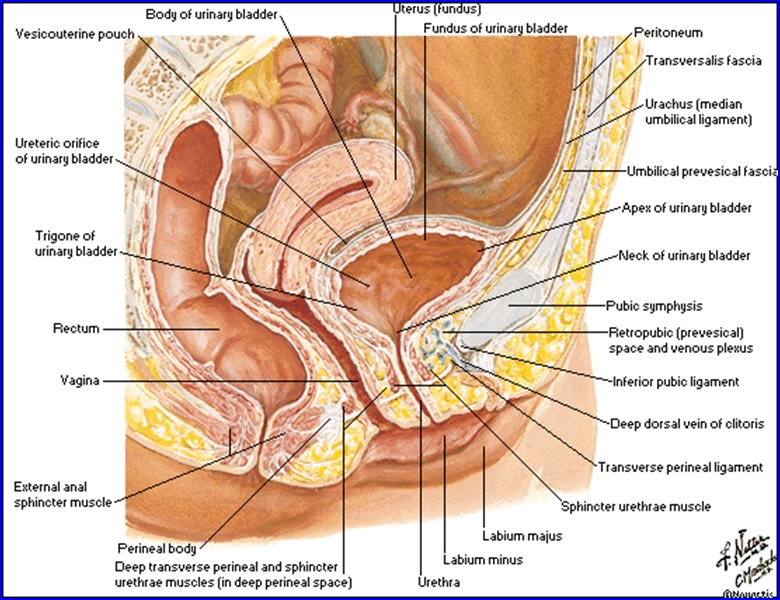

Vezica urinară- orientare şi mijloace de susţinere (secţiune medio-sagitală):